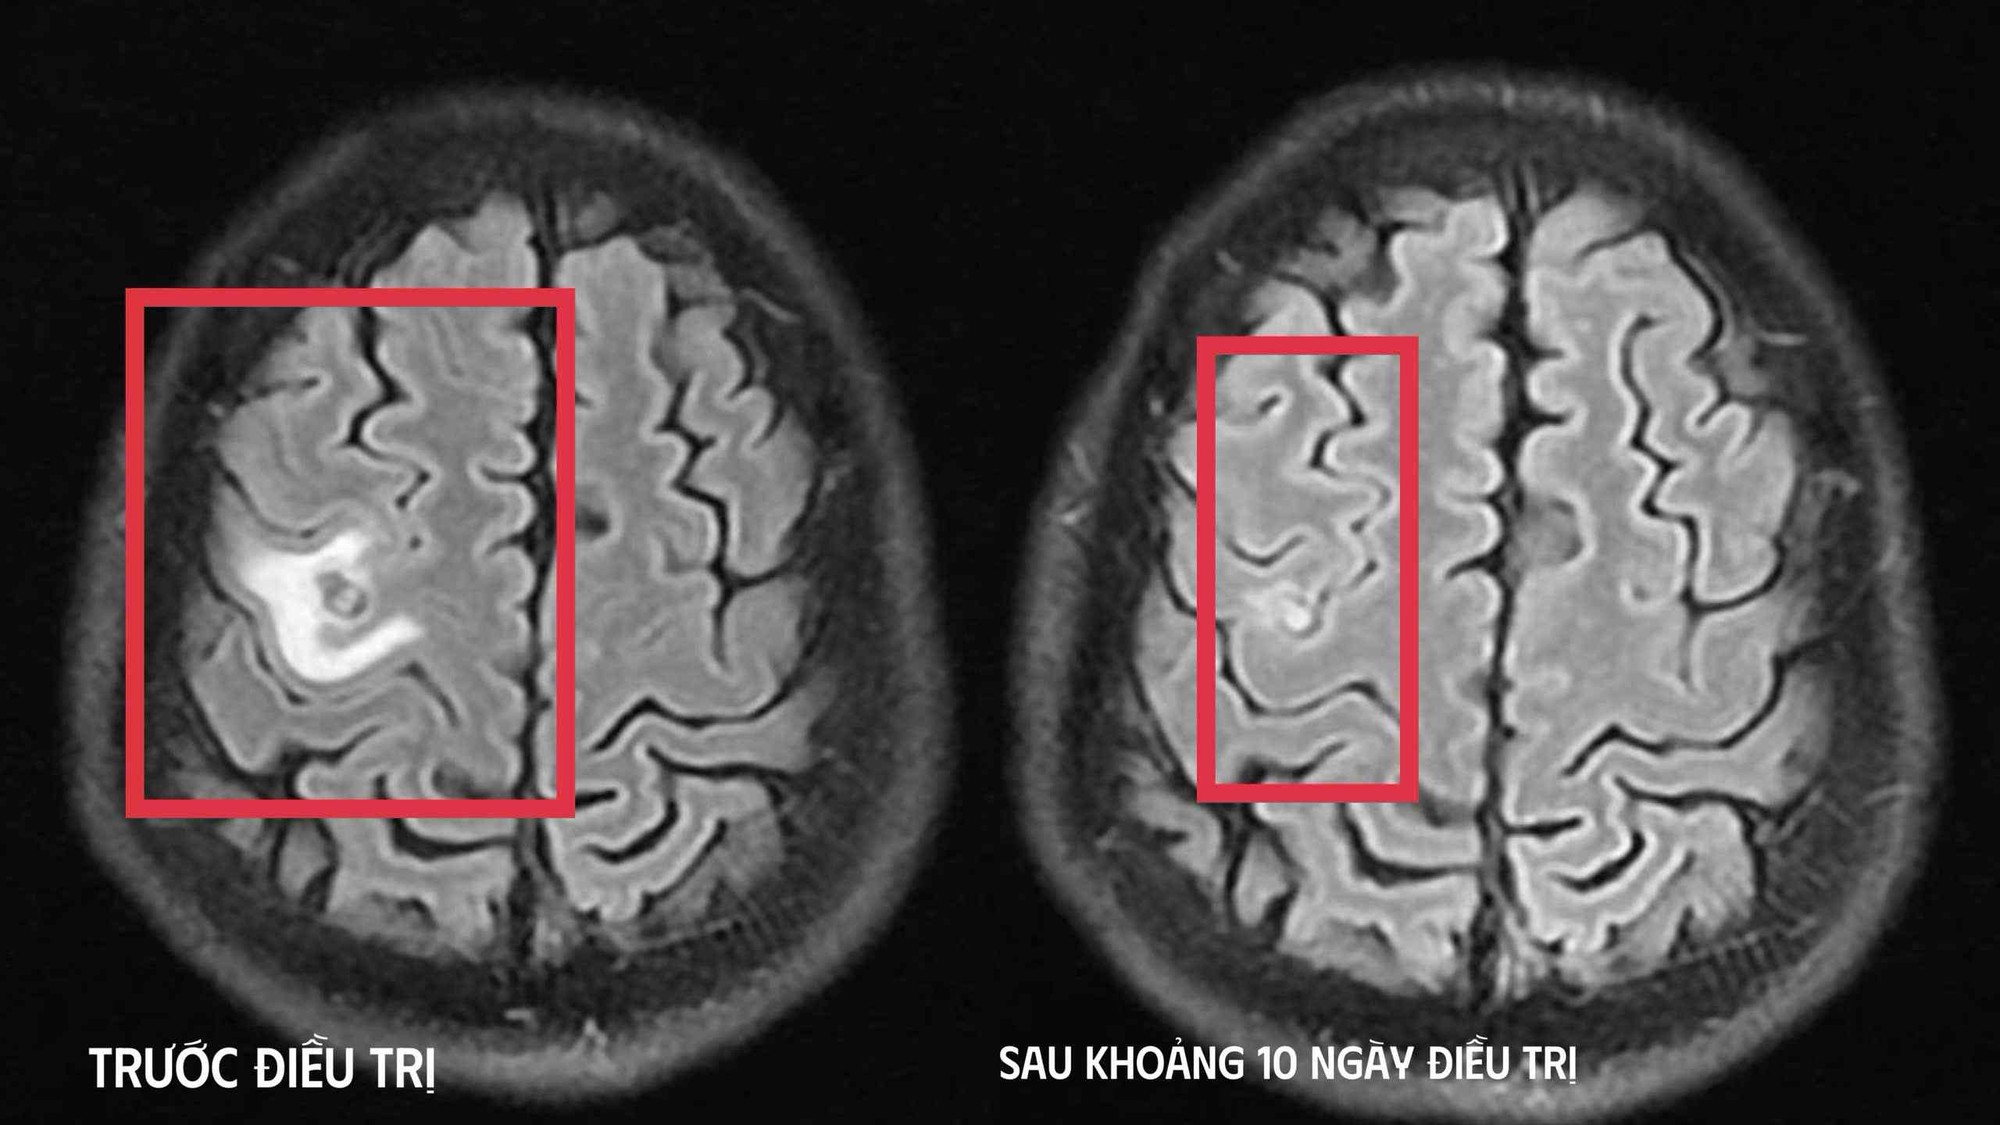

Sau khi các bác sĩ thăm khám và chụp cộng hưởng từ sọ não phát hiện một nang nhỏ ở thùy trán trái, kích thước khoảng 11 x 7 mm, kèm phù não nhẹ. Hình ảnh gợi ý tổn thương do ký sinh trùng hơn là u não nguyên phát. Xét nghiệm huyết thanh học kháng thể kháng sán dây chó dương tính, xác định chẩn đoán tổn thương não do ký sinh trùng.

Bệnh nhân được điều trị theo phác đồ, kiểm soát triệu chứng và theo dõi sát diễn biến thần kinh. Sau 10 ngày, tình trạng cải thiện rõ rệt, bệnh nhân hết tê tay, không co giật, đau đầu hay chóng mặt biến mất, toàn trạng ổn định. Bệnh nhân xuất viện và tiếp tục điều trị ngoại trú đủ liệu trình 4 tuần.

Khi tái khám gần một tháng sau, chụp cộng hưởng từ cho thấy nang não thu nhỏ rõ, phù não giảm, không còn dấu hiệu tiến triển, đáp ứng điều trị tốt.